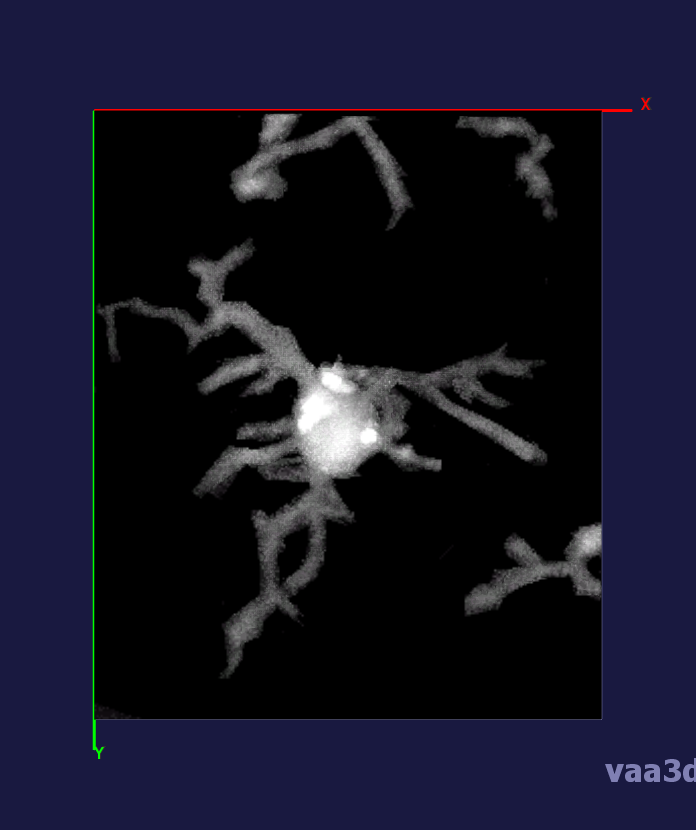

In our experiments, we compare the coupled TuFF-BFF microglia segmentation results with those given by L2S [21] and the Chan-Vese segmentation method [22]. The groundtruth in 3D was attained by manually tracing the object slice by slice from the z-stack. It must be noted that this was done by eye and could have some error. Figure 2 shows the visual comparison of the segmentation results for our dataset. Our result shown on the third column captures both the soma and processes. Figure 3 shows the Dice coefficient comparison of each segmentation method to the ground truth. Since the soma is much larger than the fine processes in the microglia, the processes have less volumetric impact on the similarity score. As explained in Section 1, segmenting the processes is important for quantifying the extension from the soma and its volume of surveillance. We use the Dice coefficient to quantitatively compare the ramification by taking the convex hull of the resulting segmentation. The Dice coefficient is a similarity measure that is computed using with where is the ground truth and is the compared image.

From Figure 4, the average Dice score for coupled TuFF-BFF was 0.77, compared to 0.53 for L2S [21] and .58 for Chan-Vese [22]. It must be noted that L2S required manual user initialization for each 2D image in the stack. While the Chan-Vese method has automatic seed selection, our coupled TuFF/BFF method was the only method that was a true 3D segmentation algorithm. L2S could not consistently capture the entire processes due to the intensity inhomogeneity throughout the object and background noise. The Chan-Vese segmentation could capture the extensions of the processes but did not work well with noise and attained false positives in the reconstruction. Since our method uses the tubular and blob information of the object to separate foreground and background, the segmentation only evolved within the object boundaries.